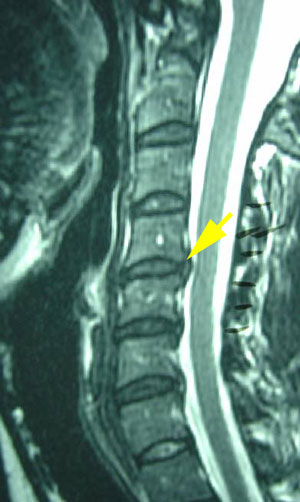

Figure 3 shows an MRI image of a cervical spine disc herniation from the side (See arrow.) which is implicated with headache pain.